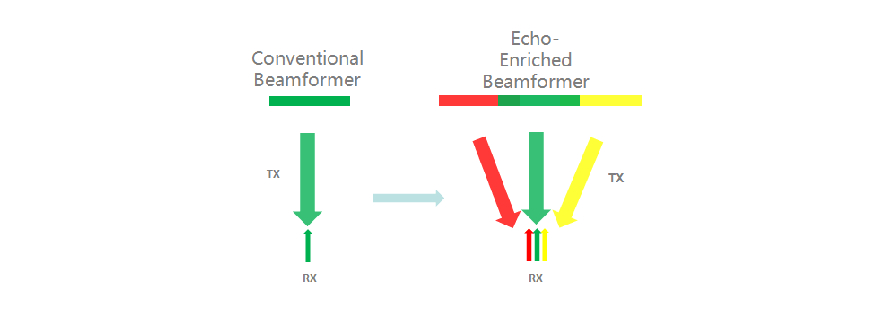

Echo Boost?

??? ?? ??? ?????? ??? ??? ?? ???? ??? ??? ?? ? ?? ??? ???? ?? ?? ??? ?????? ?? ??? ????? ???? ?? ?? ?? ?? ??? ?? ?? ?? ??? ???? ?????.